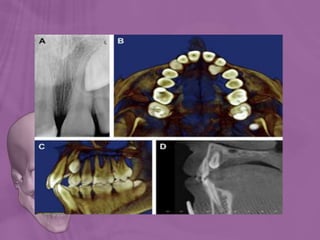

 Conventional radiography has the following short

comings,

1. Difficulty in assessing position (buccal/palatal)

2. Difficulty in assessing level and extent of resorption of

adjacent teeth

CT scan was advised

 Can determine the exact position of an

impacted tooth.

 Clear serial sections may be taken at

graduated depth.

 This technique allows the elimination of

superimposition of other structures.

Position for axial section Position for coronal section